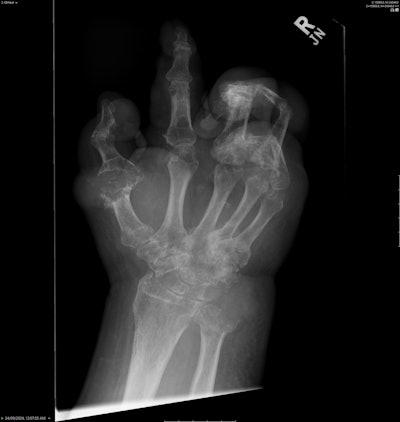

Diffuse juxta-articular erosions with overhanging edges and preserved joint spaces. Most marked at the first metatarsophalangeal joint (MTPJ) and ulnar styloid. All figures courtesy of Dr. Roland Zhang and presented at RANZCR 2025 ASM.

The exhibit described the case of a 59-year-old man who presented to the emergency department after normal working hours with severe pain throughout his body. Examination showed diffuse tophaceous gout in the hands and feet, as well as bilateral lower limb edema and paresthesia. Bedside Doppler ultrasound showed a left common femoral vein thrombus, whilst an echocardiogram showed a dilated aortic root. A double rule-out CT pulmonary angiogram (CTPA) and aortogram was organized.

Incidental note was made of widespread destructive arthropathy and multiple calcified perivertebral masses in the lower lumbar spine, and a possible bone or soft-tissue-based malignancy causing nerve compression was raised by the medical staff. Imaging was reviewed with radiology. These changes were also found in the bilateral sternoclavicular, glenohumeral, and thoracic costovertebral joints. Prior x-rays were examined, and these changes were determined to be most likely due to tophaceous gout.